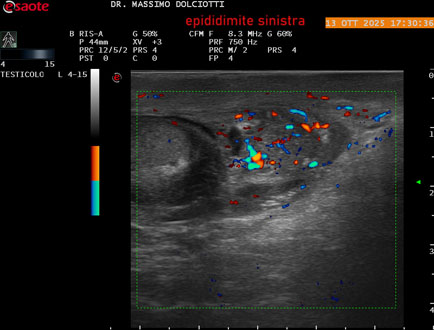

Data inserimento: 14/10/2025

Ecografia del: 13/10/2025

Strumento: Esaote MyLab Eight

Sonda: Lineare Multifrequenza 4-15 MHz

Età Paziente: M 70 anni

Motivazione dell'esame: da 2 giorni dolore al testicolo sinistro.

Commento all'esame: le immagini ed il video documentano l'epididimo sinistro spiccatamente aumentato di volume e di vascolarizzazione, come da flogosi. Didimo sinistro lievemente aumentato di volume. Quadro clinico ed ecografico da ricondurre ad epididimite acuta sinistra.

Conclusioni: epididimite acuta sinistra (acute left epididymitis).

Presentazione: Dr. Massimo Dolciotti - Ancona